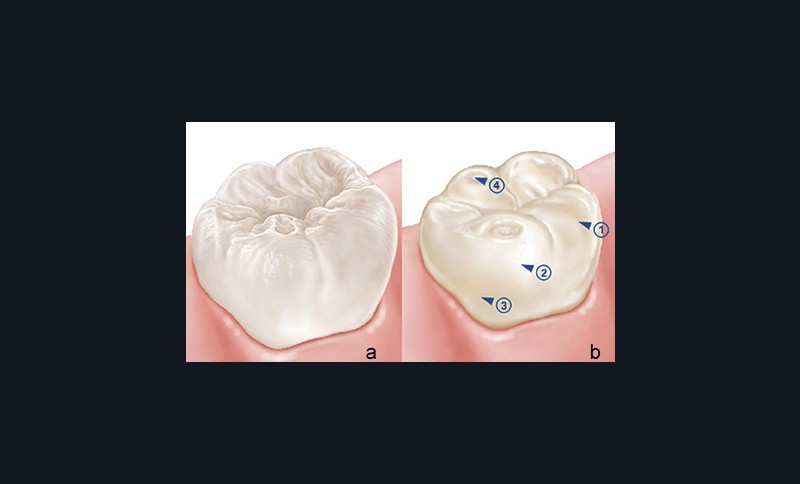

Aspect clinique(fig. 1) [5, 7-9]